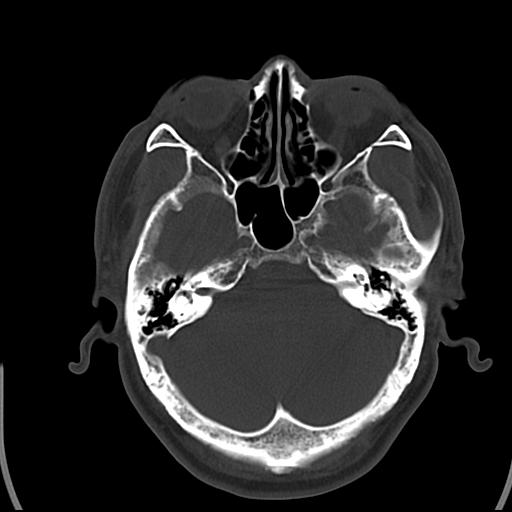

头皮下高密度结节影???临床上在老年男性比较常见。大家看看是什么?成因是? 本例患者,男性,51岁。外伤来诊。无染发史及发根植入史。

考虑异物。

皮下钙化点

没见过,可能为毛囊钙化。